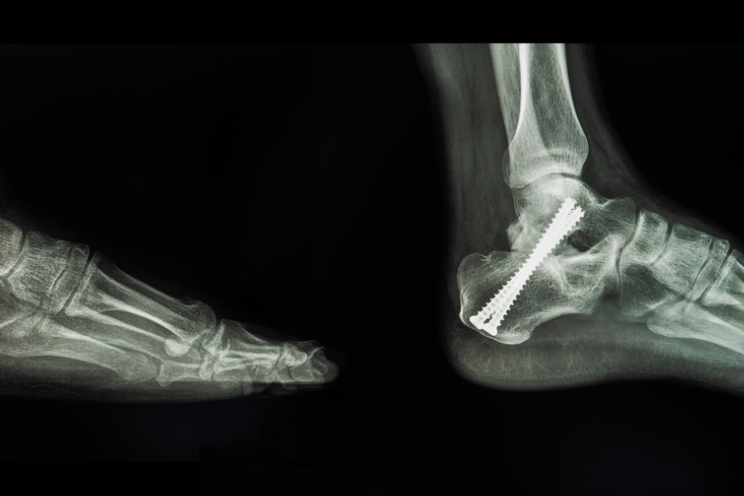

चोट और बीमारी सहित कई कारणों से बोन की ग्राफ्टिंग की जाती है। एक बोन ग्राफ्ट का उपयोग कई जटिल फ्रैक्चर के मामले में या उन लोगों के लिए किया जा सकता है जो प्रारंभिक उपचार के बाद ठीक नहीं होते हैं। हड्डी की बीमारी, संक्रमण या चोट लगने के बाद इसे किया जाता है। इसमें बोन की गुहाओं या हड्डियों के बड़े हिस्से में बोन की छोटी मात्रा का उपयोग करना शामिल हो सकता है। एक बोन ग्राफ्टिंग का उपयोग सर्जिकल रूप से प्रत्यारोपित उपकरणों के आसपास बोन को ठीक करने में मदद करने के लिए किया जा सकता है, जैसे संयुक्त प्रतिस्थापन, प्लेट्स या स्क्रू (screws)

आपका डॉक्टर यह तय करेगा कि आपकी सर्जरी से पहले किस प्रकार का बोन ग्राफ्ट इस्तेमाल करना है। आपकोल जनरल एनेस्थिसिया दिया जाएगा। जिसके बाद आपको गहरी नींद आ जाएगी। एक एनेस्थेसियोलॉजिस्ट आपके ठीक होने की निगरानी करेगा। आपका सर्जन ऊपर की त्वचा में एक चीरा लगाएगा जहां ग्राफ्ट की जरूरत होती है। फिर दान की गई बोन को आकार देते हैं। निम्नलिखित में से किसी एक का उपयोग करके बोन ग्राफ्टिंग कि जाएगी:

- पिंस (pins)

- प्लेट (plates)

- स्क्रू (screw)

- तार (wire)

- केबल (cable)